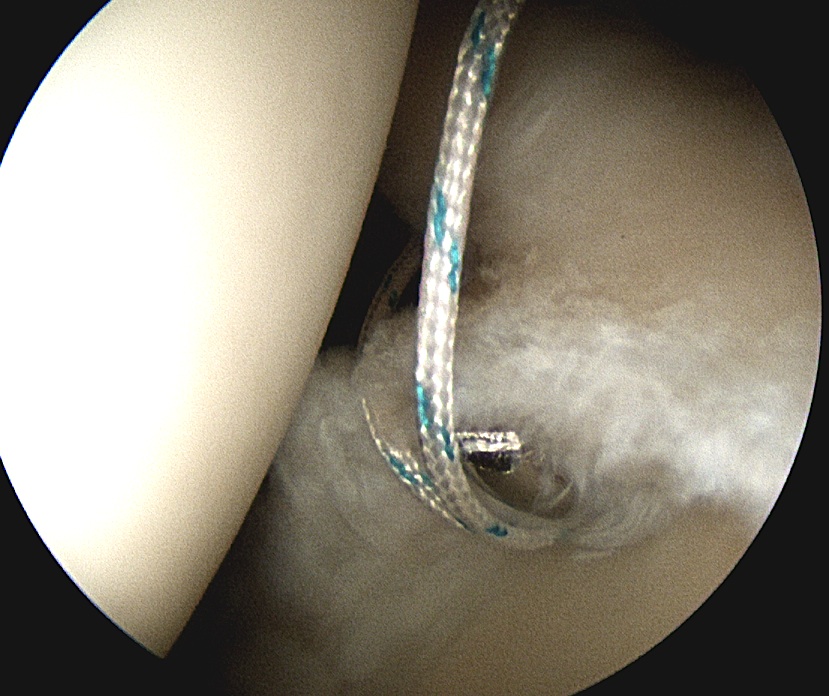

- suture passer through anterior portal (right angled for left shoulder)

Anterior anchor

- best to pass the suture passer above the biceps to get good bite

Posterior 2 anchors

- pass suture passer under biceps